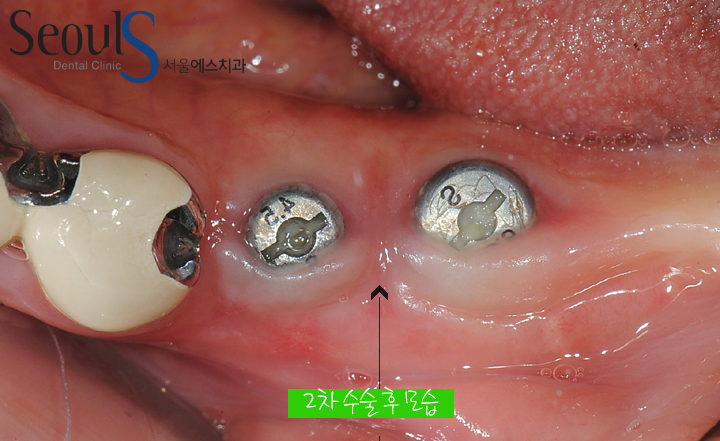

임플란트 머리 부분을 잇몸 밖으로 노출 시키는 2차 수술 후 모습입니다

치아를 제작하기 위해 본 뜨는 장치를 연결한 모습입니다